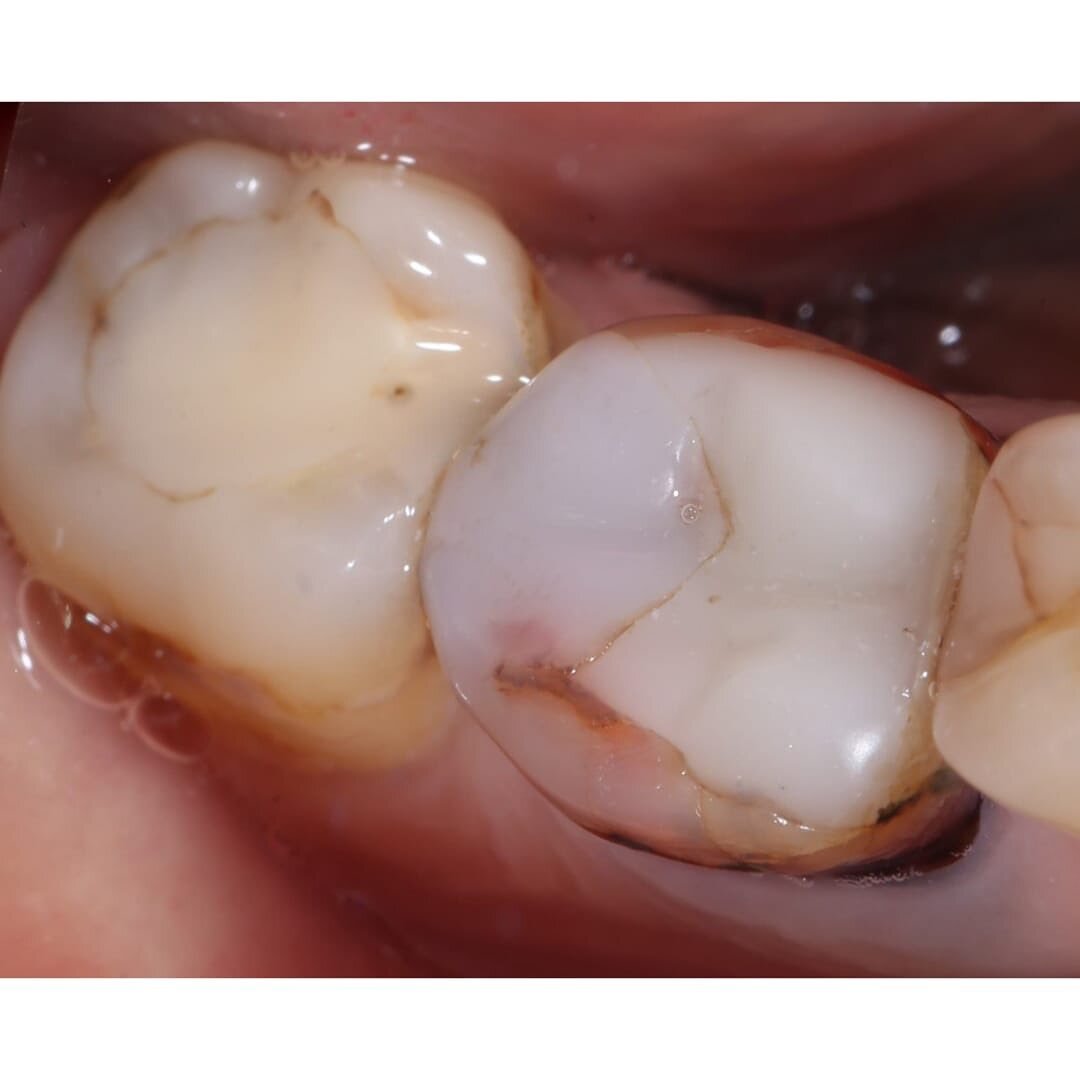

Зуб шестой.

Ранее пролечен резорцин-формалином — это устаревший способ, он не позволяет качественно запломбировать каналы и в результате в них возникает воспаление, которое впоследствии выходит за верхушку корня.

Под зубом образовалась "киста".

Зуб укреплен анкерным штифтом — это создает еще одно препятствие для перелечивания.

✔️Параллельно вылечили четвертый, пятый и седьмой зуб от кариеса.